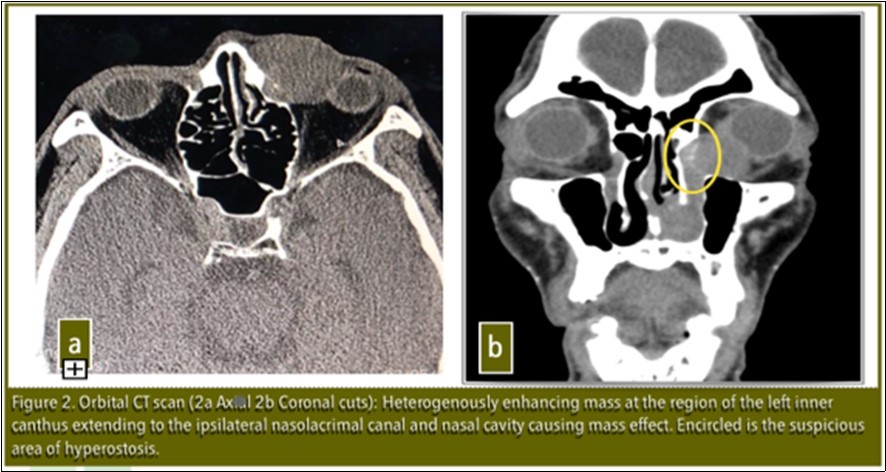

Visual acuity, slit lamp examination, extraocular eye muscle movements were unremarkable at the time of examination except for lacrimal apparatus irrigation which showed blockage at the level of the left common canaliculus. Orbital CT-scan revealed: Heterogenously enhancing mass extending to ipsilateral nasolacrimal canal and nasal cavity causing mass effect. No bone erosions present. There was note of a suspicious area of hyperostosis in the area of the lacrimal sac [Figure 2]. Patient was referred to the Department of Otolaryngology Head and Neck Surgery for co-management. Punch biopsy was done and histopathology revealed Inverting Papilloma.

Figure 2.Orbital CT scan ( 2a Axial.  2b Coronal cuts): Heterogenously enhancing mass at the region of the left inner canthus extending to the ipsilateral nasolacrimal canal and nasal cavity causing mass effect. Encircled is the suspicious area of hyperostosis.

It is important to determine the area of origin by CT scan to optimize the proper surgical management and prevent recurrence.3Lee et al in his paper in 2007 noted that there is a high correlation between the origin of the inverted papilloma and focal hyperostosis on CT scan which might facilitate prediction of tumor origin.3

In our patient, hyperostosis was noted in the area of the lacrimal sac on CT scan which was clinically correlated intraoperatively with adhesion of the mass to the bone in the lacrimal sac. This is further evidence that the origin of this tumor is in the lacrimal sac.